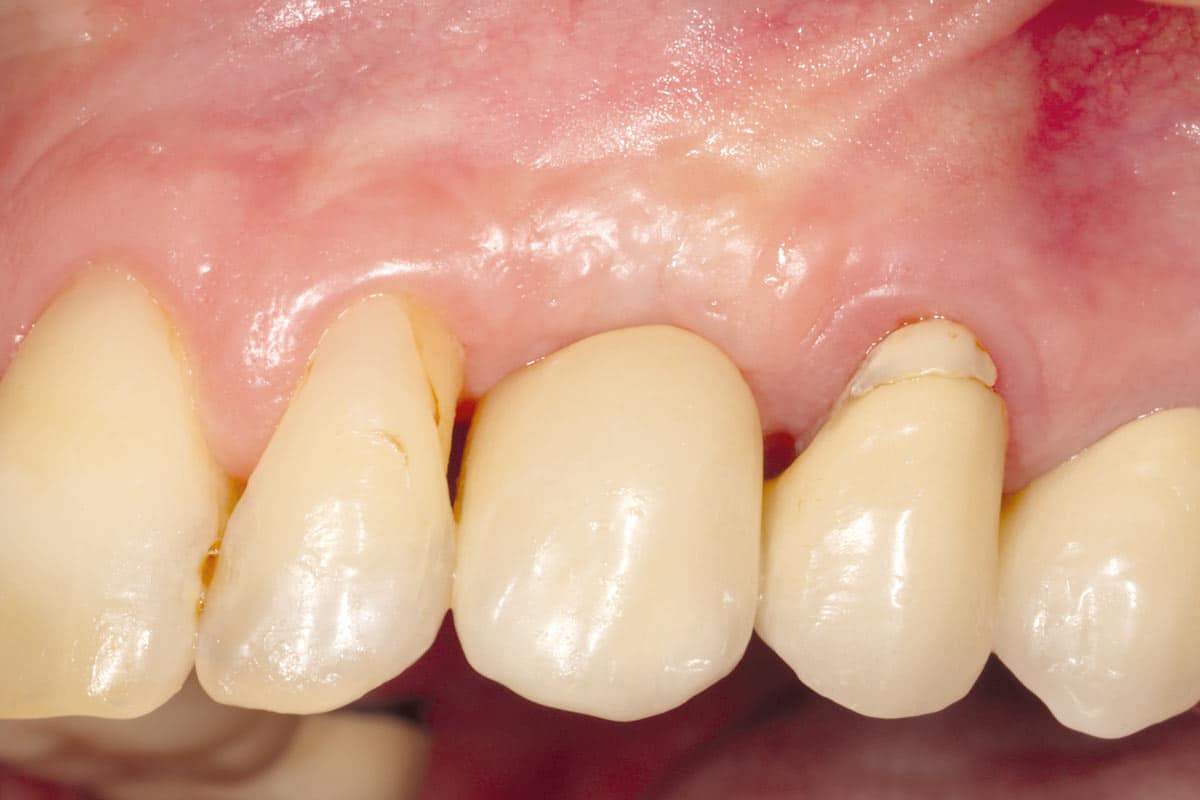

A patient presented with a peri-implant bone defect characterized by bone resorption compromising the stability and long-term prognosis of the implant. To re-establish sufficient bone volume and ensure implant longevity, a regenerative surgical intervention was performed using a guided bone regeneration (GBR) approach. The treatment featured cerabone® plus for grafting, complemented by the Shield Technique using fully resorbable magnesium-based NOVAMag® SHIELD to guide bone regeneration.

At the 6-month follow-up, clinical and radiographic evaluations demonstrated pronounced new bone formation and favourable soft tissue integration, indicating successful regenerative outcomes. By the 12-month follow-up, bone regeneration had advanced even further, and implant stability was significantly strengthened, confirming the procedure’s lasting success. A CBCT scan at 6 months revealed promising results, which were even more striking at the 12-month mark, demonstrating optimal bone integration and implant stability.